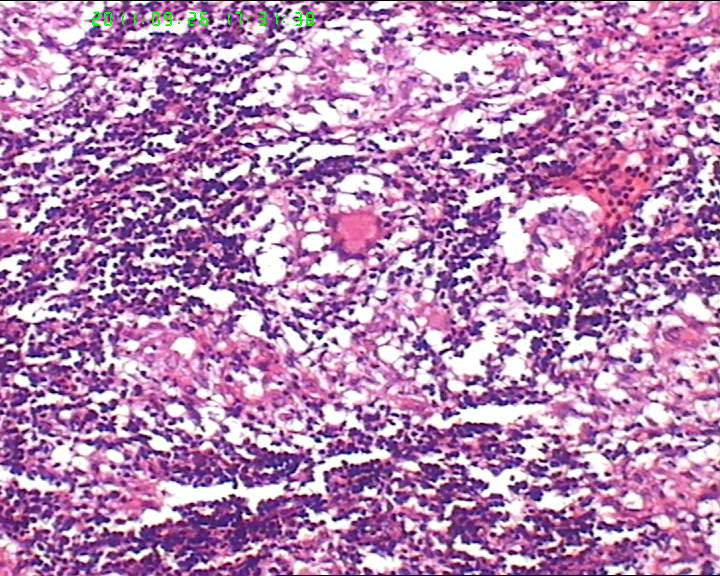

21岁女性左侧颌下淋巴结,该诊断什么?

灰白不整形肿物一个,大小3.5*2.5*2cm,包膜完整。

21岁女性左侧颌下淋巴结,该诊断什么?图2

慢性肉芽肿性炎症,形态学倾向结节病,但是作为病理工作者对于这样的病例,再结合咋们国情,还是建议临床除外增殖性结核后再考虑结节病。

肉芽肿性炎症,倾向结节病。

肉芽肿性炎,考虑结核不除外结节病